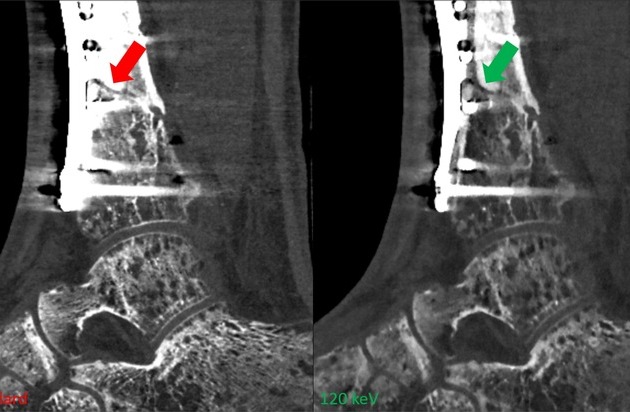

Abbildung 1: Standardbilder (links) und virtuelle monoenergetische Bilder (120 keV, rechts) einer Computertomographie mit Zinnfilter. Die monoenergetischen Bilder zeigen eine deutlich verbesserte Visualisierung des Frakturspalts (Pfeile). / © Universitätsklinik Balgrist

Figure 1: Standard image (left) and virtual monoenergetic image (120 keV, right) of a photon counting computed tomography scan of the ankle with tin prefiltration. The monoenergetic image shows a significantly improved visualization of the fracture gap (arrows).